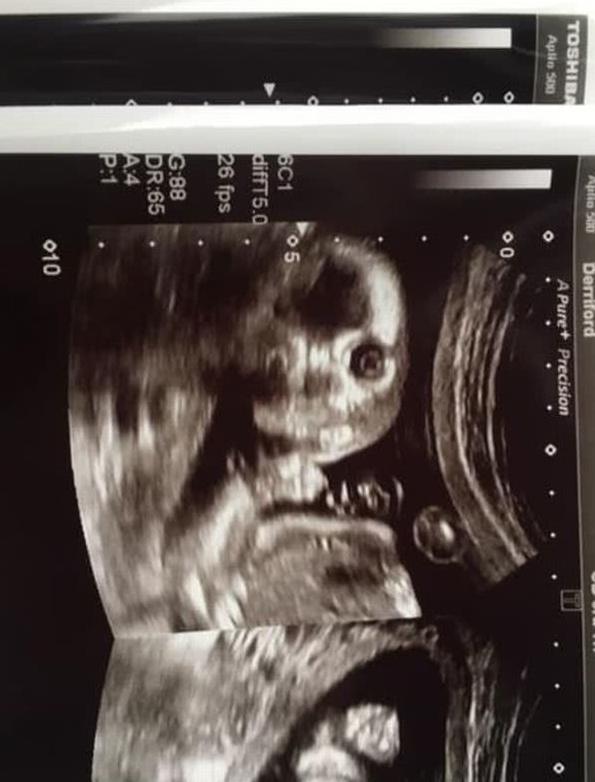

2月13日,英国《太阳报》登载了一张可爱的B超照片,照片中,小胎儿居然直视镜头,看起来像个小鬼般精灵可爱。

格里尔也是一位准妈妈,在做孕20周例行检查时,医生为胎儿做了B超扫描。

不过做B超时,医生和格里尔都吃了一惊,因为格里尔腹中的小宝宝突然转了一个位置,目光直视镜头,看起来很机灵、别具神采。医生说这样的情形是很罕见的。

做B超时,格里尔42岁的丈夫克林特·琼斯(Clint Jones)也在场,两人起初都觉得有点“恐怖”、有点震惊,但很快,两人都笑了起来。

格里尔将她宝宝的可爱B超照片发布在社交媒体上,配文说,大家都看过许多标准的、可爱的B超扫描照片,但她的宝宝照片有点罕见,非常有趣。